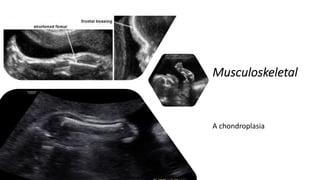

Musculoskeletal

A chondroplasia

achondroplasia

young boy with achondroplasia has:

1. short stature,

2. short limbs and fingers,

3. normal length of trunk,

4. bowed legs,

5. a relatively large head,

6. a prominent forehead,

7. and a depressed nasal bridge